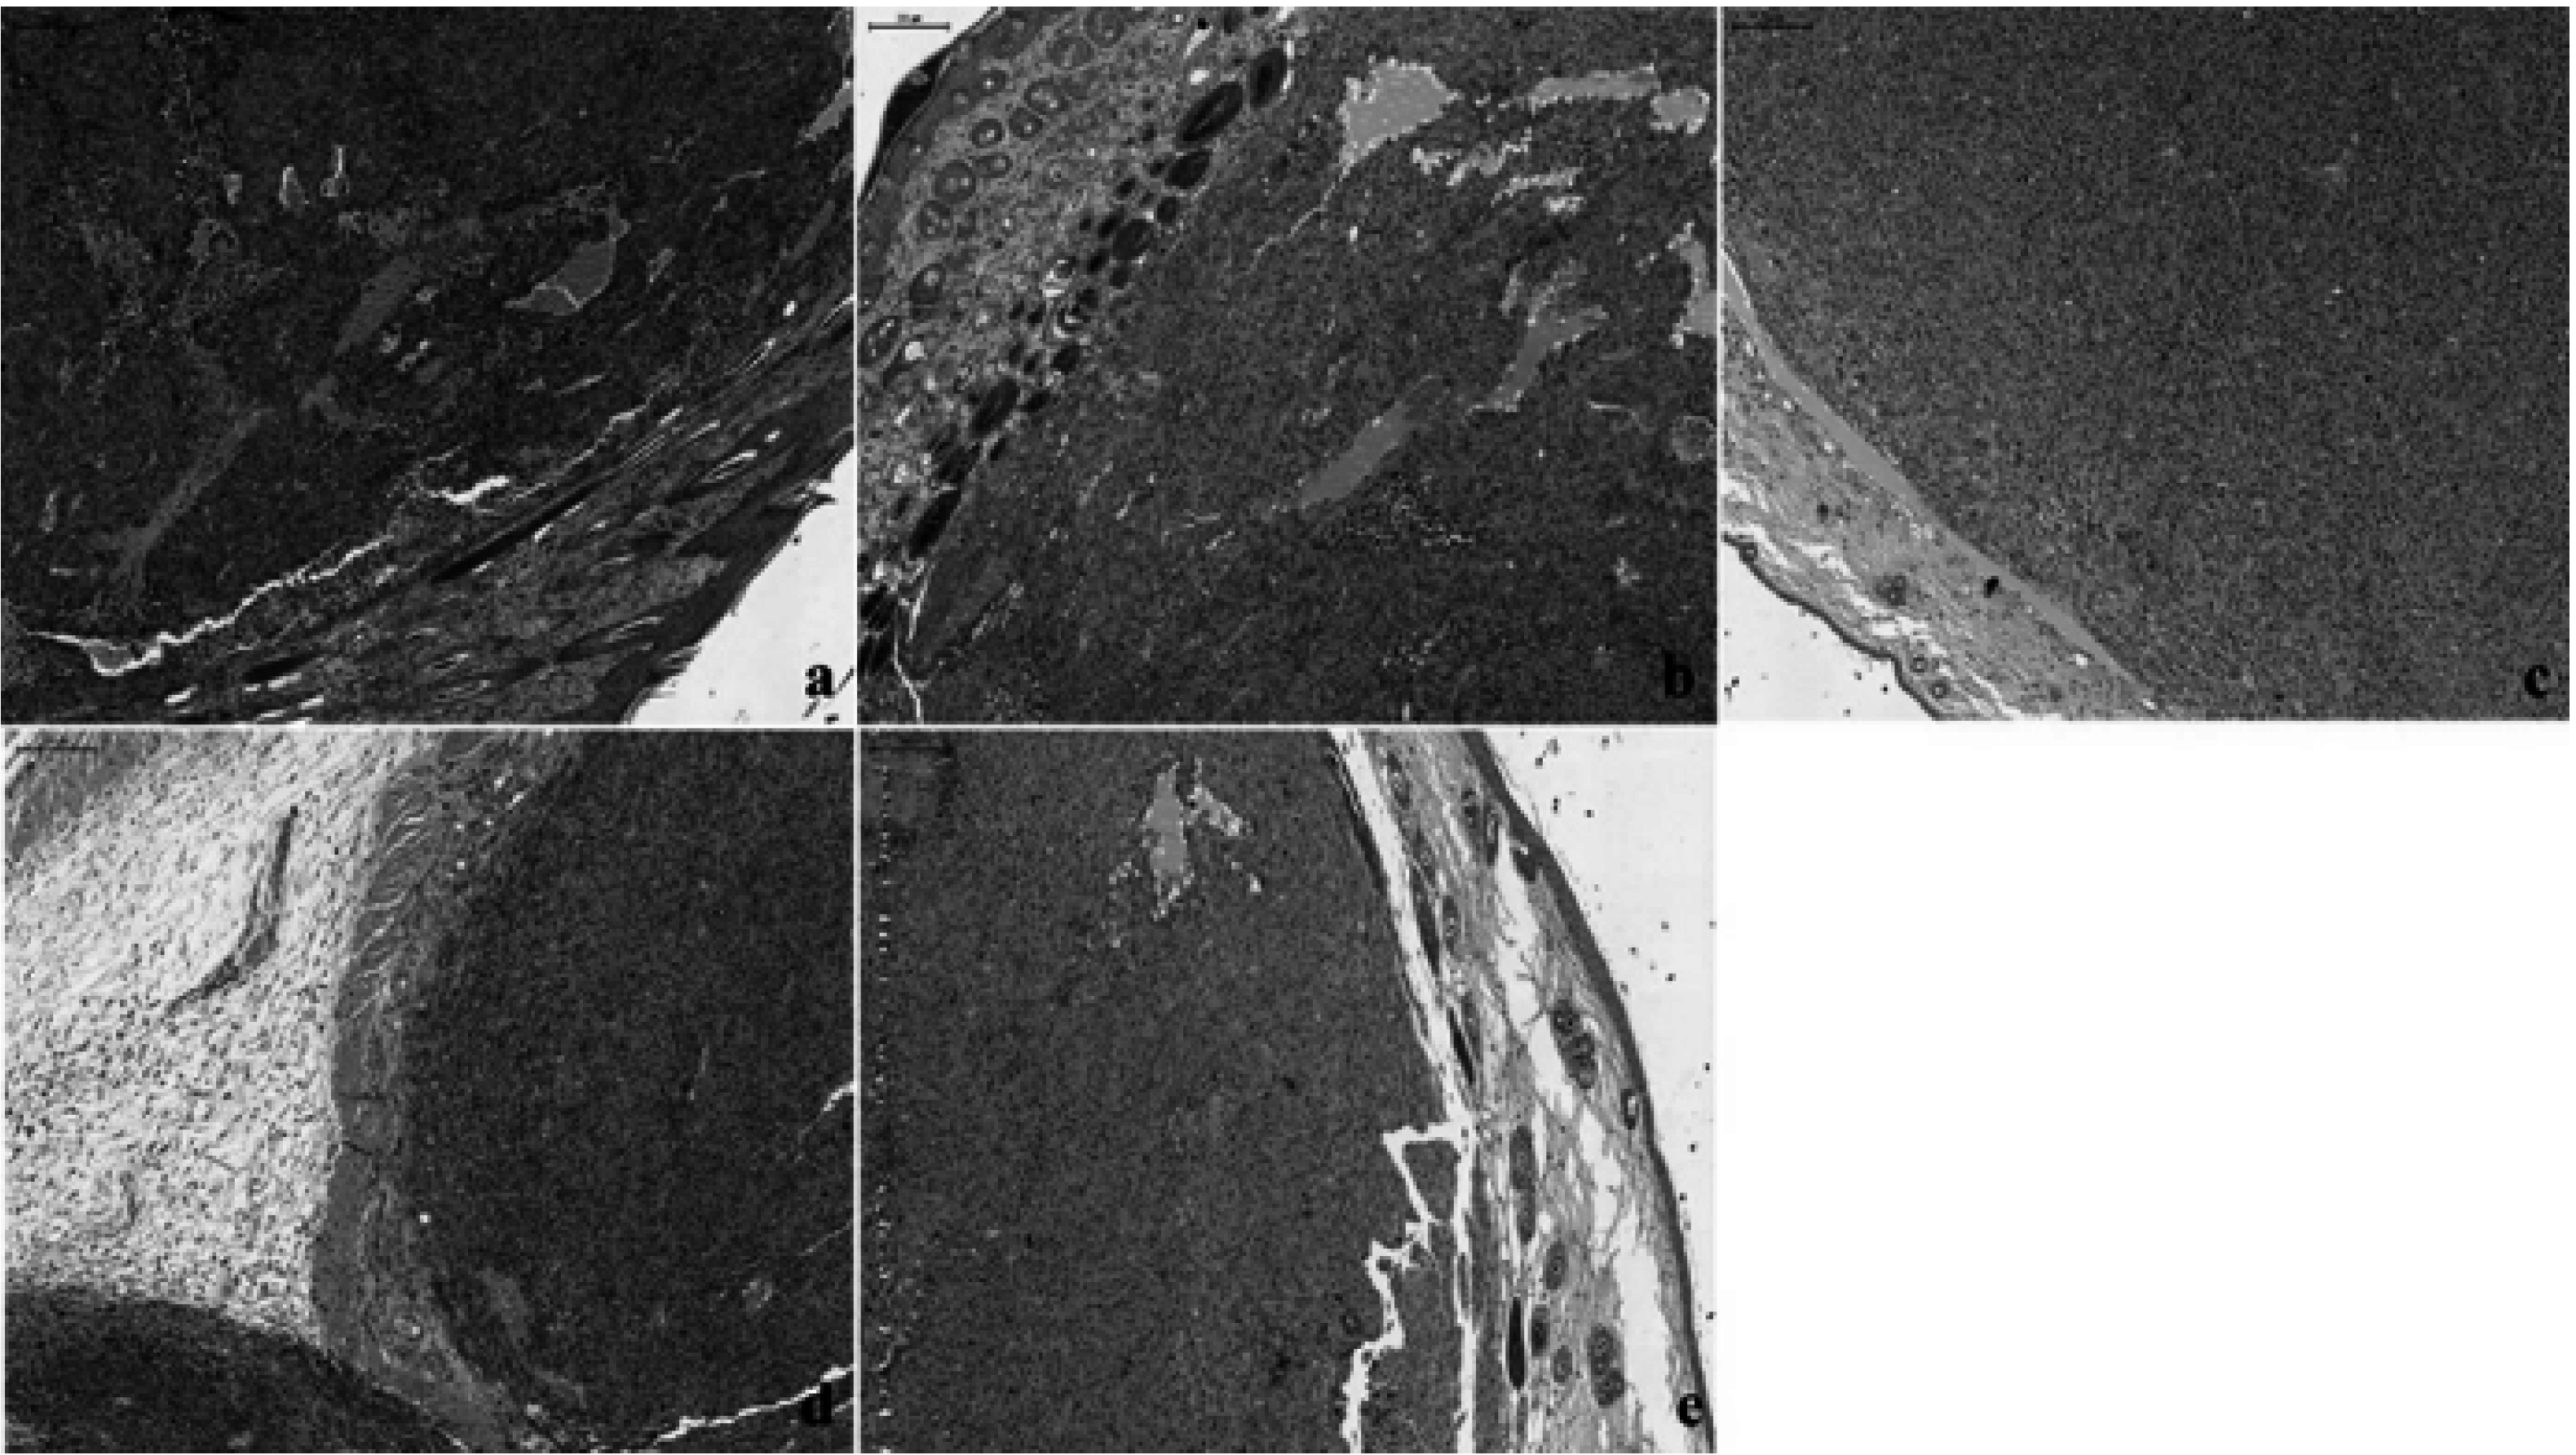

2.3. Histological and Immunohistochemical Results